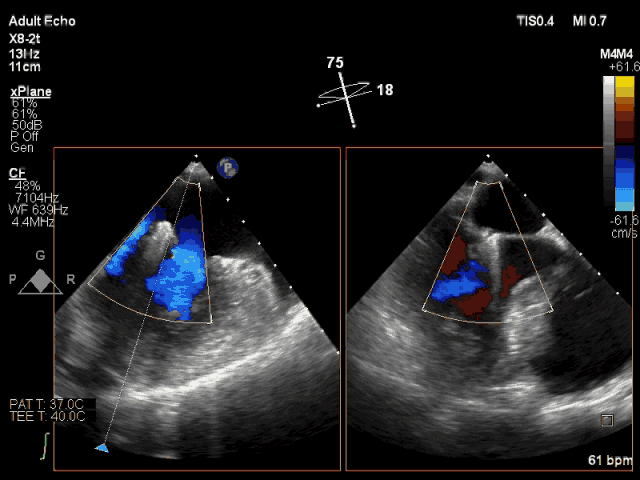

夾合即刻CDFI示輕微MR

此次轉(zhuǎn)播心臟超聲機(jī)器為最新一代Philips EPIQ 7C,使用X8-2t食道探頭進(jìn)行術(shù)中經(jīng)食道超聲,采用TrueVue實(shí)時(shí)三維雙容積視野同時(shí)顯示二尖瓣左房觀和左室觀。新一代超聲機(jī)器分辨率高、圖像處理速度快、圖像界面舒適,使得手術(shù)非常順利,手術(shù)轉(zhuǎn)播的導(dǎo)管操作時(shí)間僅用8分鐘?;颊咝g(shù)后即刻效果滿意,反流從重度減少到輕度。